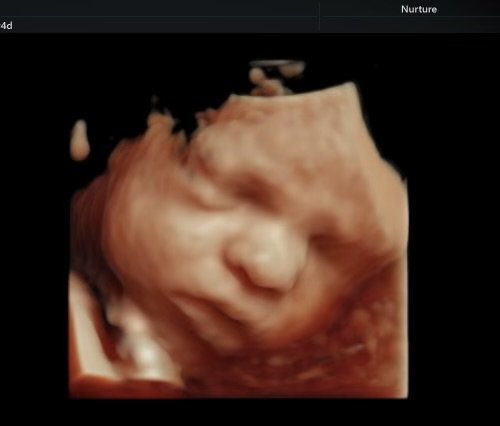

Seeing your baby suck their thumb, purse their little lips together, rub their eyes, and kick their little feet is magical.

Ultrasound image of a fetus inside the womb.

During your session, you’ll watch your baby in real time—seeing their movements, their expressions, their unique rhythms. These are moments of life in utero that are usually unseen, yet deeply felt. Many families describe it as the first time everything becomes real in a new way.

• 2D & 3D are still images, while 4D/HD adds the dimension of motion, so it looks like a video. HD is the newest fetal keepsake ultrasound technology on the market. HD allows you to see all the details of the baby by using software technology to change the focal points and "lighting" of the ultrasound.